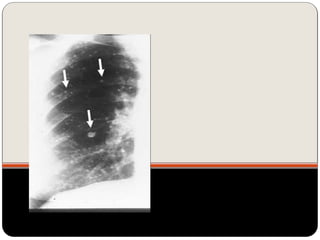

Nódulos pulmonares múltiplos

 Causas mais comum em adultos:

neoplasia metastática (diversos diâmetros,

densidade de tecido mole, raramente calcificada, exceto

osteossarcoma)

doença infecciosa (fúngicas e micobacterianas);

Carcinoma de tireóide com metástases pulmonares;